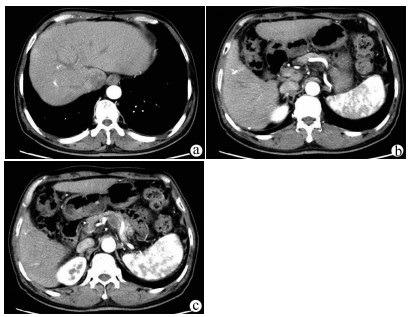

Clinical features, diagnosis, and treatment of IgG4-associated sclerosing cholangitis

2021, 37(8): 1883-1887. DOI: 10.3969/j.issn.1001-5256.2021.08.026

Abstract(1332) HTML (583) PDF (2114KB)(94)

Abstract:

Objective  To investigate the clinical features, diagnosis, and treatment of IgG4-associated sclerosing cholangitis (IgG4-SC).  Methods  A retrospective analysis was performed for the clinical data of 25 patients who were diagnosed with IgG4-SC in Beijing YouAn Hospital, Capital Medical University, from January 2014 to September 2020, and an electronic medical record system was used to collect general information, medical history, diagnosis and treatment processes, laboratory examination, imaging data, and pathological data. Clinical features, process of confirmed diagnosis, and cause of misdiagnosis were analyzed. Normally distributed continuous data were expressed as mean±SD, and the non-normally distributed continuous data were expressed as M(Pminimum value-Pmaximum value).  Results  Among the 25 patients with IgG4-SC, there were 21 (84%) male patients, and the mean age was 57.61±9.73 years. Common initial symptoms included jaundice and/or yellow urine in 18 patients (78.26%) and weakness in 9 patients (39.13%). As for imaging classification, 16 patients (64%) had type Ⅰ IgG4-SC, no patient had type Ⅱa IgG4-SC, 4 (16%) had IIb IgG4-SC, 1 (4%) had type Ⅲ IgG4-SC, and 4 (16%) had type Ⅳ IgG4-SC. Pancreatic involvement was observed in 22 patients (88%). Glucocorticoids were the main treatment method, and total bilirubin achieved a mean reduction of 67.48% within 2 weeks. Among the 22 patients with a confirmed diagnosis in our hospital, 15 (68.18%) were suspected of "space-occupying lesions in the pancreatic and biliary system" and 5 (22.73%) were suspected of obstructive jaundice at the outpatient service. Understanding of IgG4-SC was achieved by postoperative pathology in the early stage, then imaging doctors gradually became aware of this disease, and finally multidisciplinary consultation made more physicians understand the disease, which helped to make a confirmed diagnosis earlier.  Conclusion  For patients with obstructive jaundice, clinical physicians need to identify IgG4-SC based on clinical manifestations and especially imaging features. Multidisciplinary consultation involving imaging and pathology plays an important role in helping clinicians understand this disease and making a confirmed diagnosis.